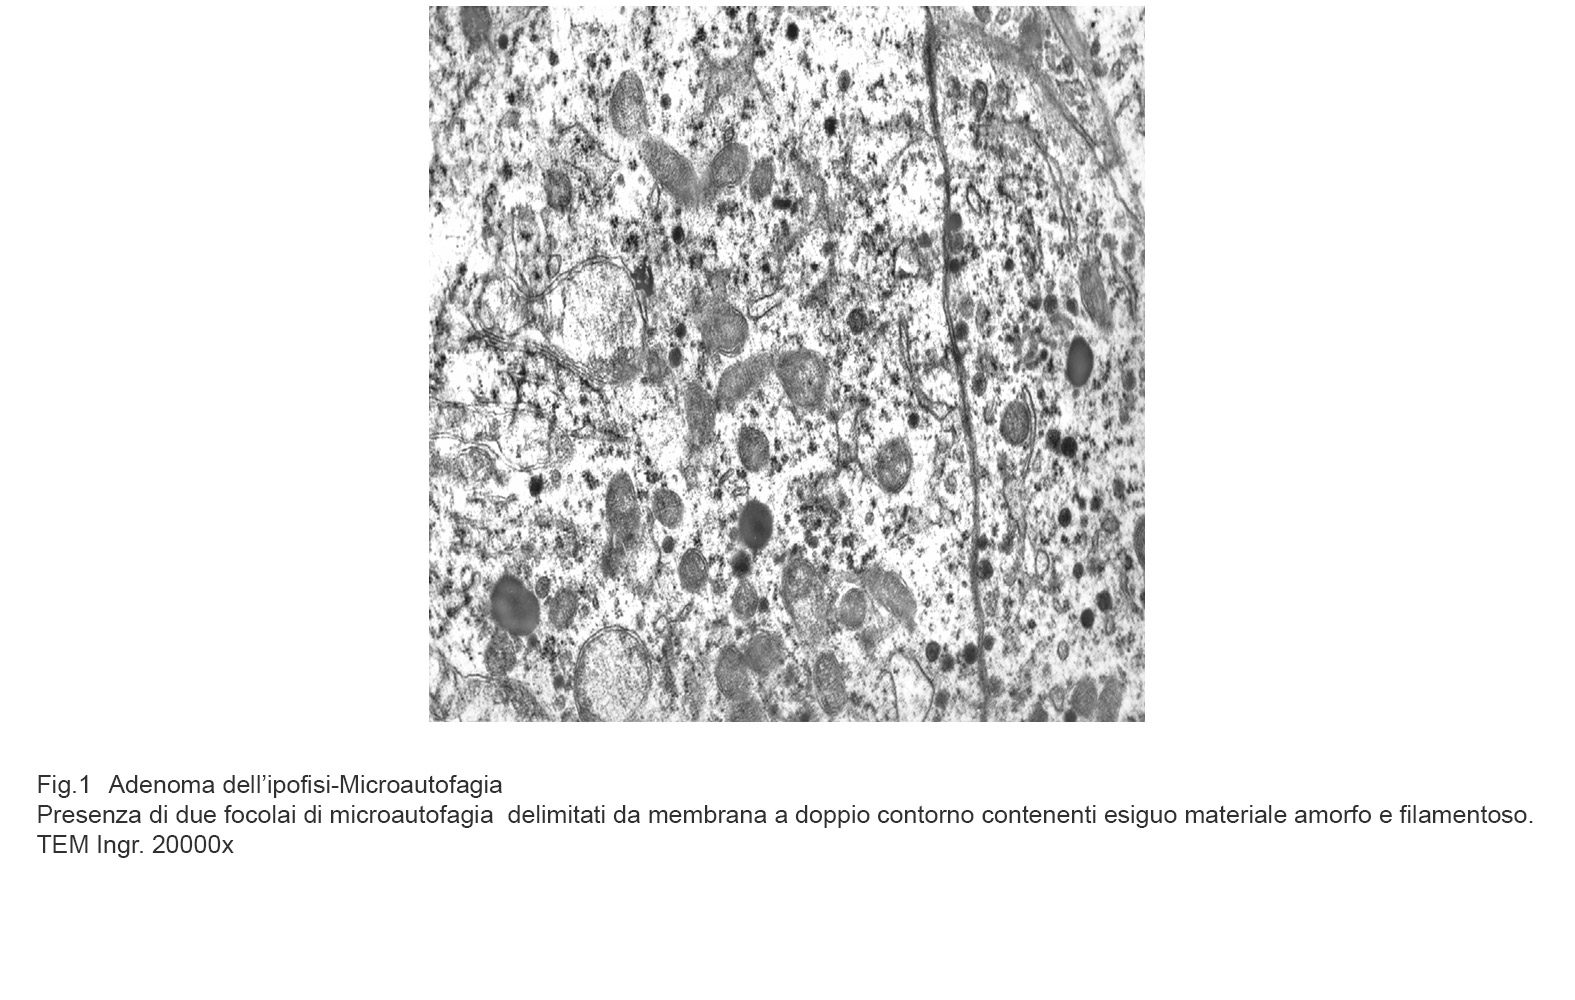

MICROAUTOFAGIA

I focolai di microautofagia si ritrovano frequentemente commisti a mitocondri disfunzionali e a reticolo- endoplasmatico in stato di stress.

Essi sono di piccole dimensioni, appaiono come vescicole, delimitate da una membrana a doppio strato, immerse nel citosol e

ricolme di materiale amorfo oppure di materiale amorfo commisto a frammenti filamentosi.

Fig.1a